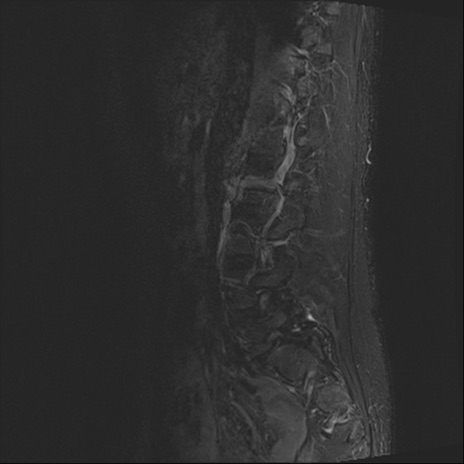

【整形】TIPS症例4 腰椎MRI STIR(矢状断像)

腰椎MRI

T2WI(矢状断像)